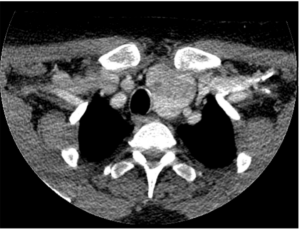

TC cervicotorácico con contraste.